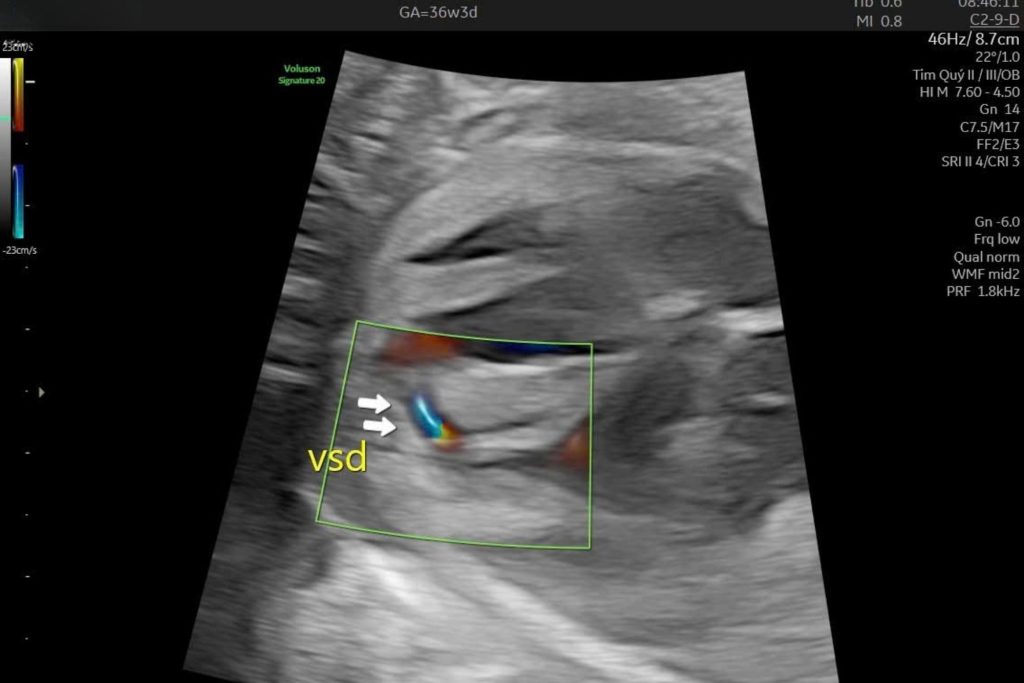

Chị H. mang thai 24 tuần đến phòng khám Dr Tú y học bào thai để siêu âm hình thái. Thai phát triển phù hợp tuổi thai, các cơ quan khác bình thường. Nhưng trong phần tim thai, bác sĩ ghi nhận một lỗ nhỏ ở vách ngăn giữa hai buồng thất.

Kết luận ghi: nghi ngờ thông liên thất phần cơ, kích thước 2 mm.

Thông liên thất phần cơ là một dạng dị tật tim bẩm sinh, trong đó có một lỗ nhỏ ở phần cơ của vách ngăn giữa hai buồng thất.

Thông liên thất phần cơ là lỗ nằm ở phần cơ dày của vách ngăn. Đây là vị trí có khả năng tự đóng cao hơn so với phần màng.

Khi nghi ngờ thông liên thất phần cơ, cần phân biệt giữa phát hiện sàng lọc và chẩn đoán xác định.

- Sàng lọc: nghi ngờ có lỗ nhỏ dựa trên siêu âm thường quy

- Chẩn đoán: được xác nhận qua siêu âm tim thai chuyên sâu